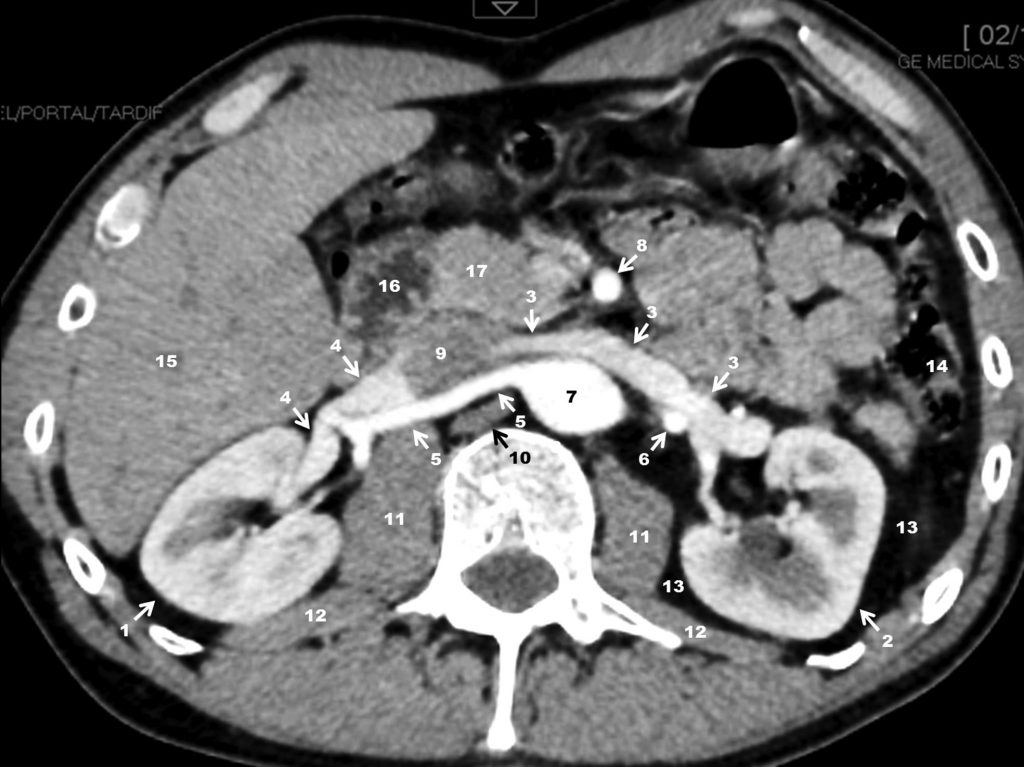

Fig. 19.9. Scanner rénal avec injection de produit de contraste à la phase artérielle (ou corticomédullaire) 40 secondes après injection. Coupe passant par le hile et le pédicule des reins.

1. Rein droit. 2. Rein gauche. 3. Veine rénale gauche. 4. Veine rénale droite. 5. Artère rénale droite. 6. Artère rénale gauche. 7. Aorte. 8. Artère mésentérique supérieure. 9. Veine cave inférieure. 10. Pilier du diaphragme. 11. Muscles psoas. 12. Muscle carré des lombes. 13. Graisse périrénale. 14. Côlon descendant. 15. Lobe droit du foie (segment VI). 16. Duodénum (portion descendante, D2). 17. Tête du pancréas.

Source : CERF, CNEBMN, 2022.